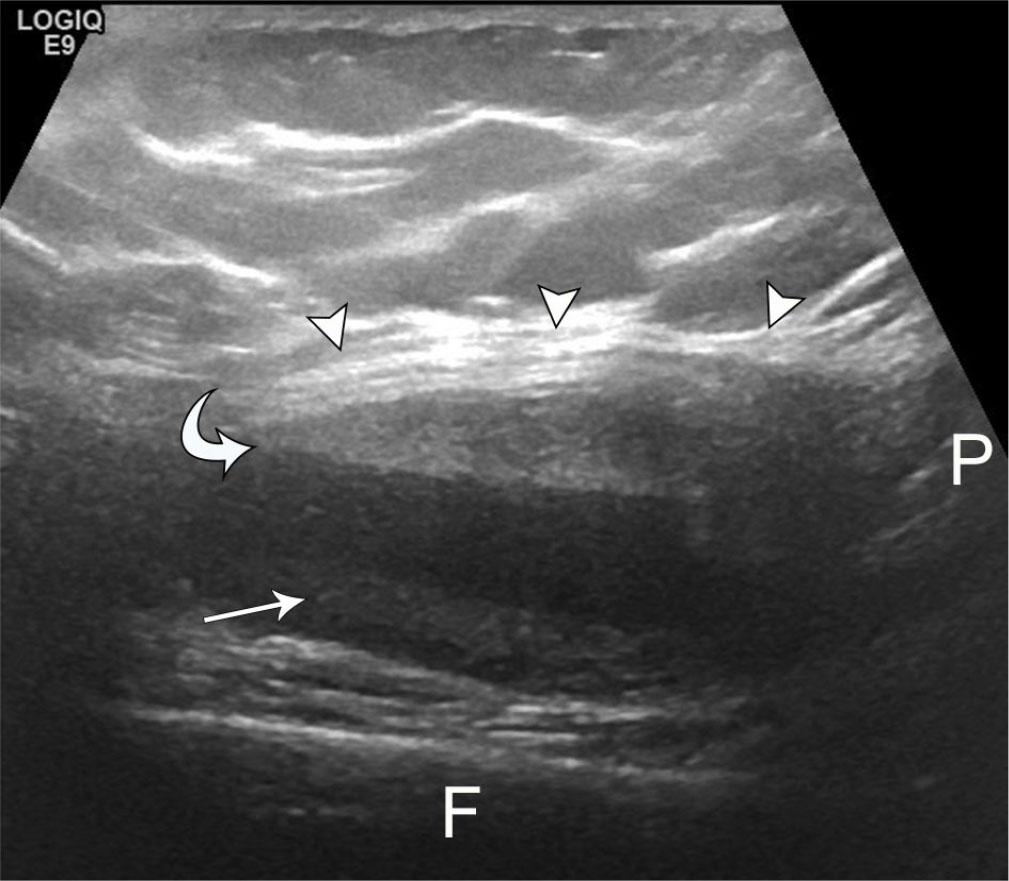

Snapping also occurs in the post-arthroplasty setting, most frequently resulting from patellar clunk syndrome(45). Within months or a few years post-arthroplasty, affected patients notice a painful catching sensation or audible snap in the suprapatellar region during knee extension. The condition results from impingement of a suprapatellar fibrous nodule against the intercondylar notch of the femoral prosthesis(48). The presence of metallic artifact on MRI limits visibility of this fibrotic nodule. On US, the abnormal tissue is typically identified as a hyperechoic nodule at the junction between the superior patellar pole and quadriceps tendon, with visible motion as the knee is extended from a flexed position and the nodule displaces from the intercondylar notch (Fig. 14)(49). Uncommonly, the nodule may be positioned immediately posterior to the patella, limiting its visibility(50).

Fig. 14.

63-year-old female with patellar clunk syndrome. Longitudinal grayscale US image shows ovoid and nodular echogenic foci (arrowheads) closely associated with the patella and quadriceps fat pad, located between the superficial quadriceps tendon and echogenic distal femoral arthroplasty hardware (arrow). Technical limitations prevented visualization of nodule motion, but dynamic evaluation elicited discomfort and characteristic clunk